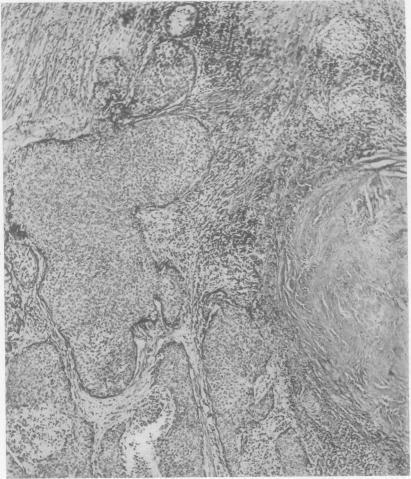

A report of two cases of sarcoidosis with bronchial carcinoma.

Thorax. 1954 Dec;9(4):291-8. doi: 10.1136/thx.9.4.291.